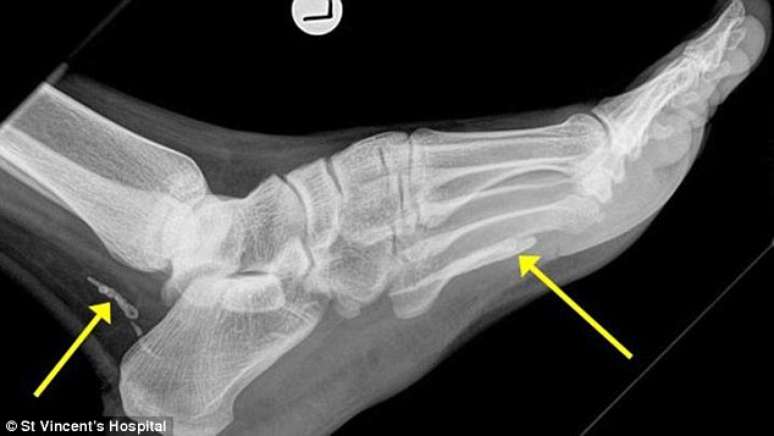

Um imigrante do Sudão que mora em Melbourne, na Austrália, resolveu visitar um médico por conta de inchaço e dores em um dos pés. No consultório, ele foi submetido a exame de raio-x e descobriu um nada agradável motivo para o desconforto: um verme de 1 metro de comprimento estava vivendo dentro dele. As informações são do Daily Mail.

De acordo com a publicação, o verme, característico de algumas regiões africanas, só pode ter sido "contraído" na terra natal do paciente - que ele não visita há mais de 4 anos. Segundo o médico que o atendeu, Dr Jonathan Darby, a criatura entrou em seu organismo ainda na fase de larva, provavelmente através de água contaminada. Em seguida, "cavou" um caminho até a sola do pé, morreu e começou a se degenerar.